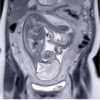

Female Acute Abdominal-Pelvic Pain – Positive Pregnancy Test – Liina Poder, MD

Female Acute Abdominal-Pelvic Pain – Negative Pregnancy Test – Liina Poder, MD

Abdominal-Pelvic Emergencies in a Pregnant Patient – Liina Poder, MD